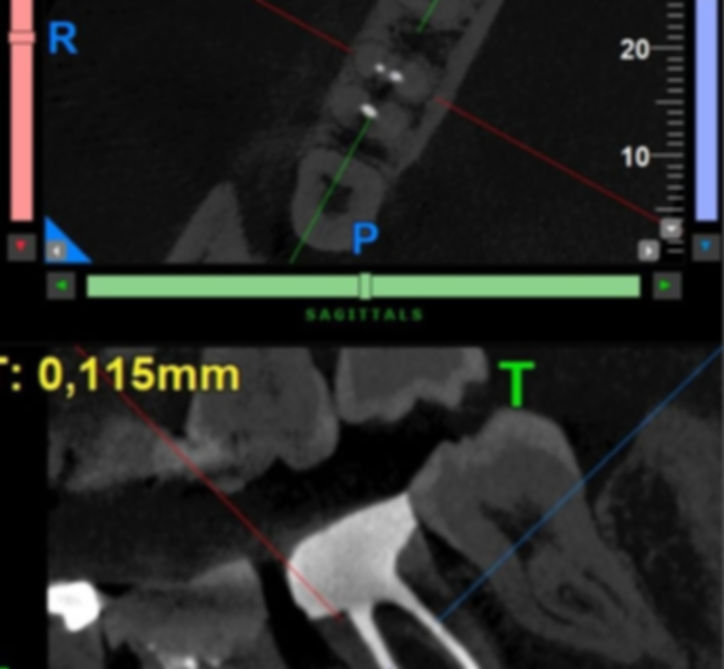

Dr. Carlos Saramago, as an Endodontist, treats his patients with the aid of an Operating Microscope. To diagnose, he uses CBCT, which allows images that traditional X-rays do not. It works like a GPS, with a specific map of your tooth.

This 3D imaging technology provides a detailed, three-dimensional reconstruction of a tooth's anatomy, which is a significant improvement over traditional X-rays.

Dr. Saramago utilizes this technology to obtain a comprehensive view of the tooth's canal system, helping to ensure a more accurate diagnosis and treatment.

The technology acts as a "GPS" for the tooth, allowing the detection of hidden infections or micro-canals that could compromise the success of a root canal.

In line with European guidelines, Dr. Saramago consistently requests a CBCT scan before any endodontic procedure to fully understand the complexity of the treatment.